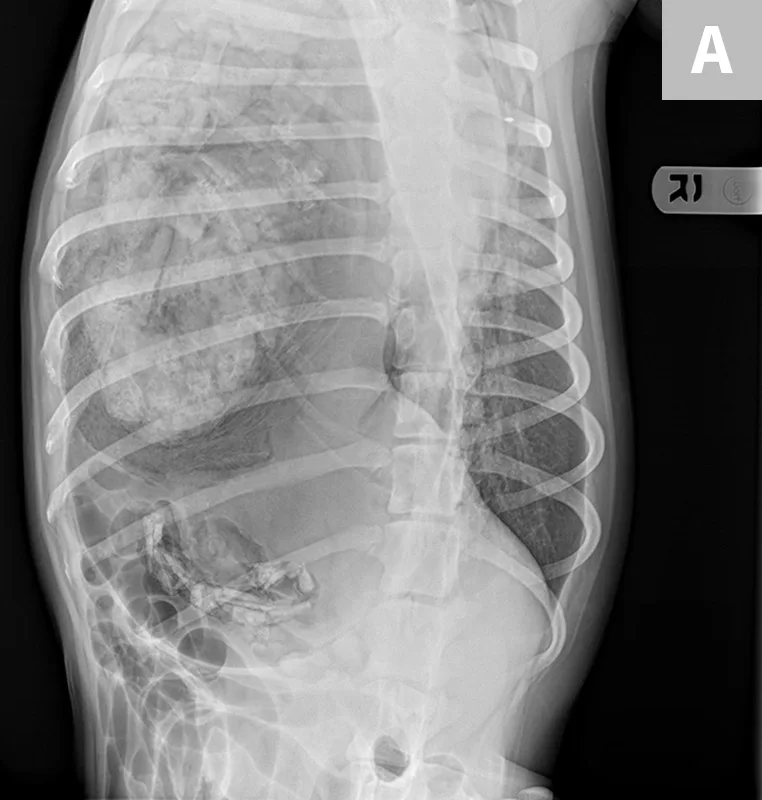

FIGURE 3A

(A) Right lateral and (B) dorsoventral radiographs of a 2-year-old spayed dog following blunt motor vehicle trauma. The diaphragmatic margins are obscured—most notably on the right side, where there is herniation of abdominal viscera into the thoracic cavity consistent with diaphragmatic hernia. The presence of tubular gas suggests some of the herniated abdominal structures are intestinal.

Any patient with blunt trauma should undergo thoracic radiography to evaluate the integrity of the diaphragm and to identify other potential traumatic injuries such as pulmonary contusions, pneumothorax, pleural effusion, pneumomediastinum, or rib fractures (Figure 3). However, the integrity of the diaphragm and thoracic contents may be difficult to interpret, and additional modalities (eg, thoracic ultrasonography, CT; Figure 4) may be necessary for definitive diagnosis.5